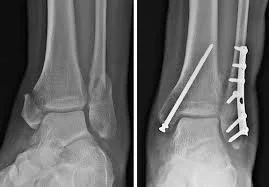

Surgical fracture treatment addresses unstable, displaced, or complex fractures of the foot and ankle. The goal is to restore anatomy, alignment, and joint congruity to allow proper healing and function.

Fracture treatment typically involves open reduction and internal fixation, using plates, screws, or other fixation devices to stabilize the fracture. The specific technique depends on fracture location and severity.